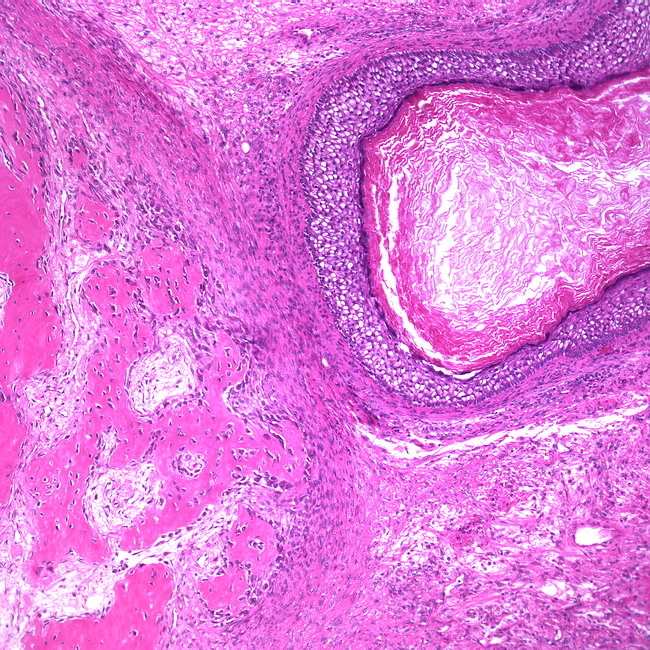

Кистозная тератома выглядит как гладкий крупный узел. При разрезе будут видны крупные кисты с различным содержимым (слизь, кашеобразная масса, мутная жидкость). В полостях можно обнаружить различные включения (костные, хрящевые, иногда бывает опухоль с волосами или зубами).

Солидная тератома имеет вид гладкого плотного или, наоборот, бугристого узла. При разрезе будет видна светло-серая, неоднородная, с небольшими кистами и включениями плотного характера, ткань. Включения могут быть из костной или хрящевой ткани.

Тератомы незрелые при разрезе представляют собой небольшие кисты светло-серого цвета, содержимое которых может состоять из незрелого эпителия, нейрогенного эпителия, хрящевой ткани и поперечнополосатых мышц.

Тератома яичника. Такой диагноз встречается чаще тератомы яичка. Среди всех новообразований яичника такой диагноз встречается в 20% случаев. В основном это узлы кистозного строения, но бывают и незрелые тератомы. Так как тератома яичника протекает часто бессимптомно, то, как правило, ее обнаруживают при диагностике другого заболевания. Обычно активизация этого вида опухоли приходится на периоды гормональной перестройки (период полового созревания, реже – при наступлении климакса). В удаленных яичниках можно найти различные включения – зубы, волосы.